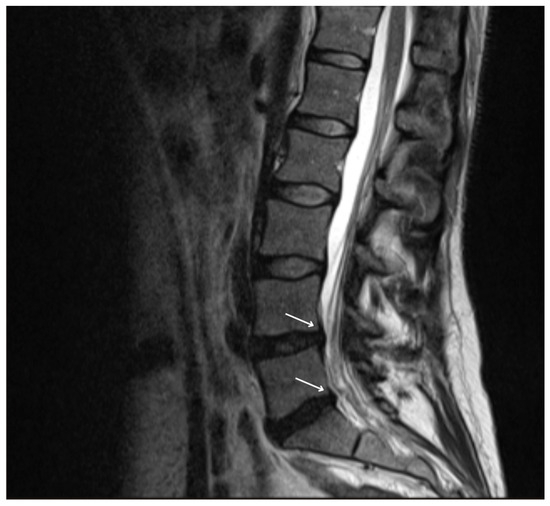

2. Case Report

4.4. Investigations